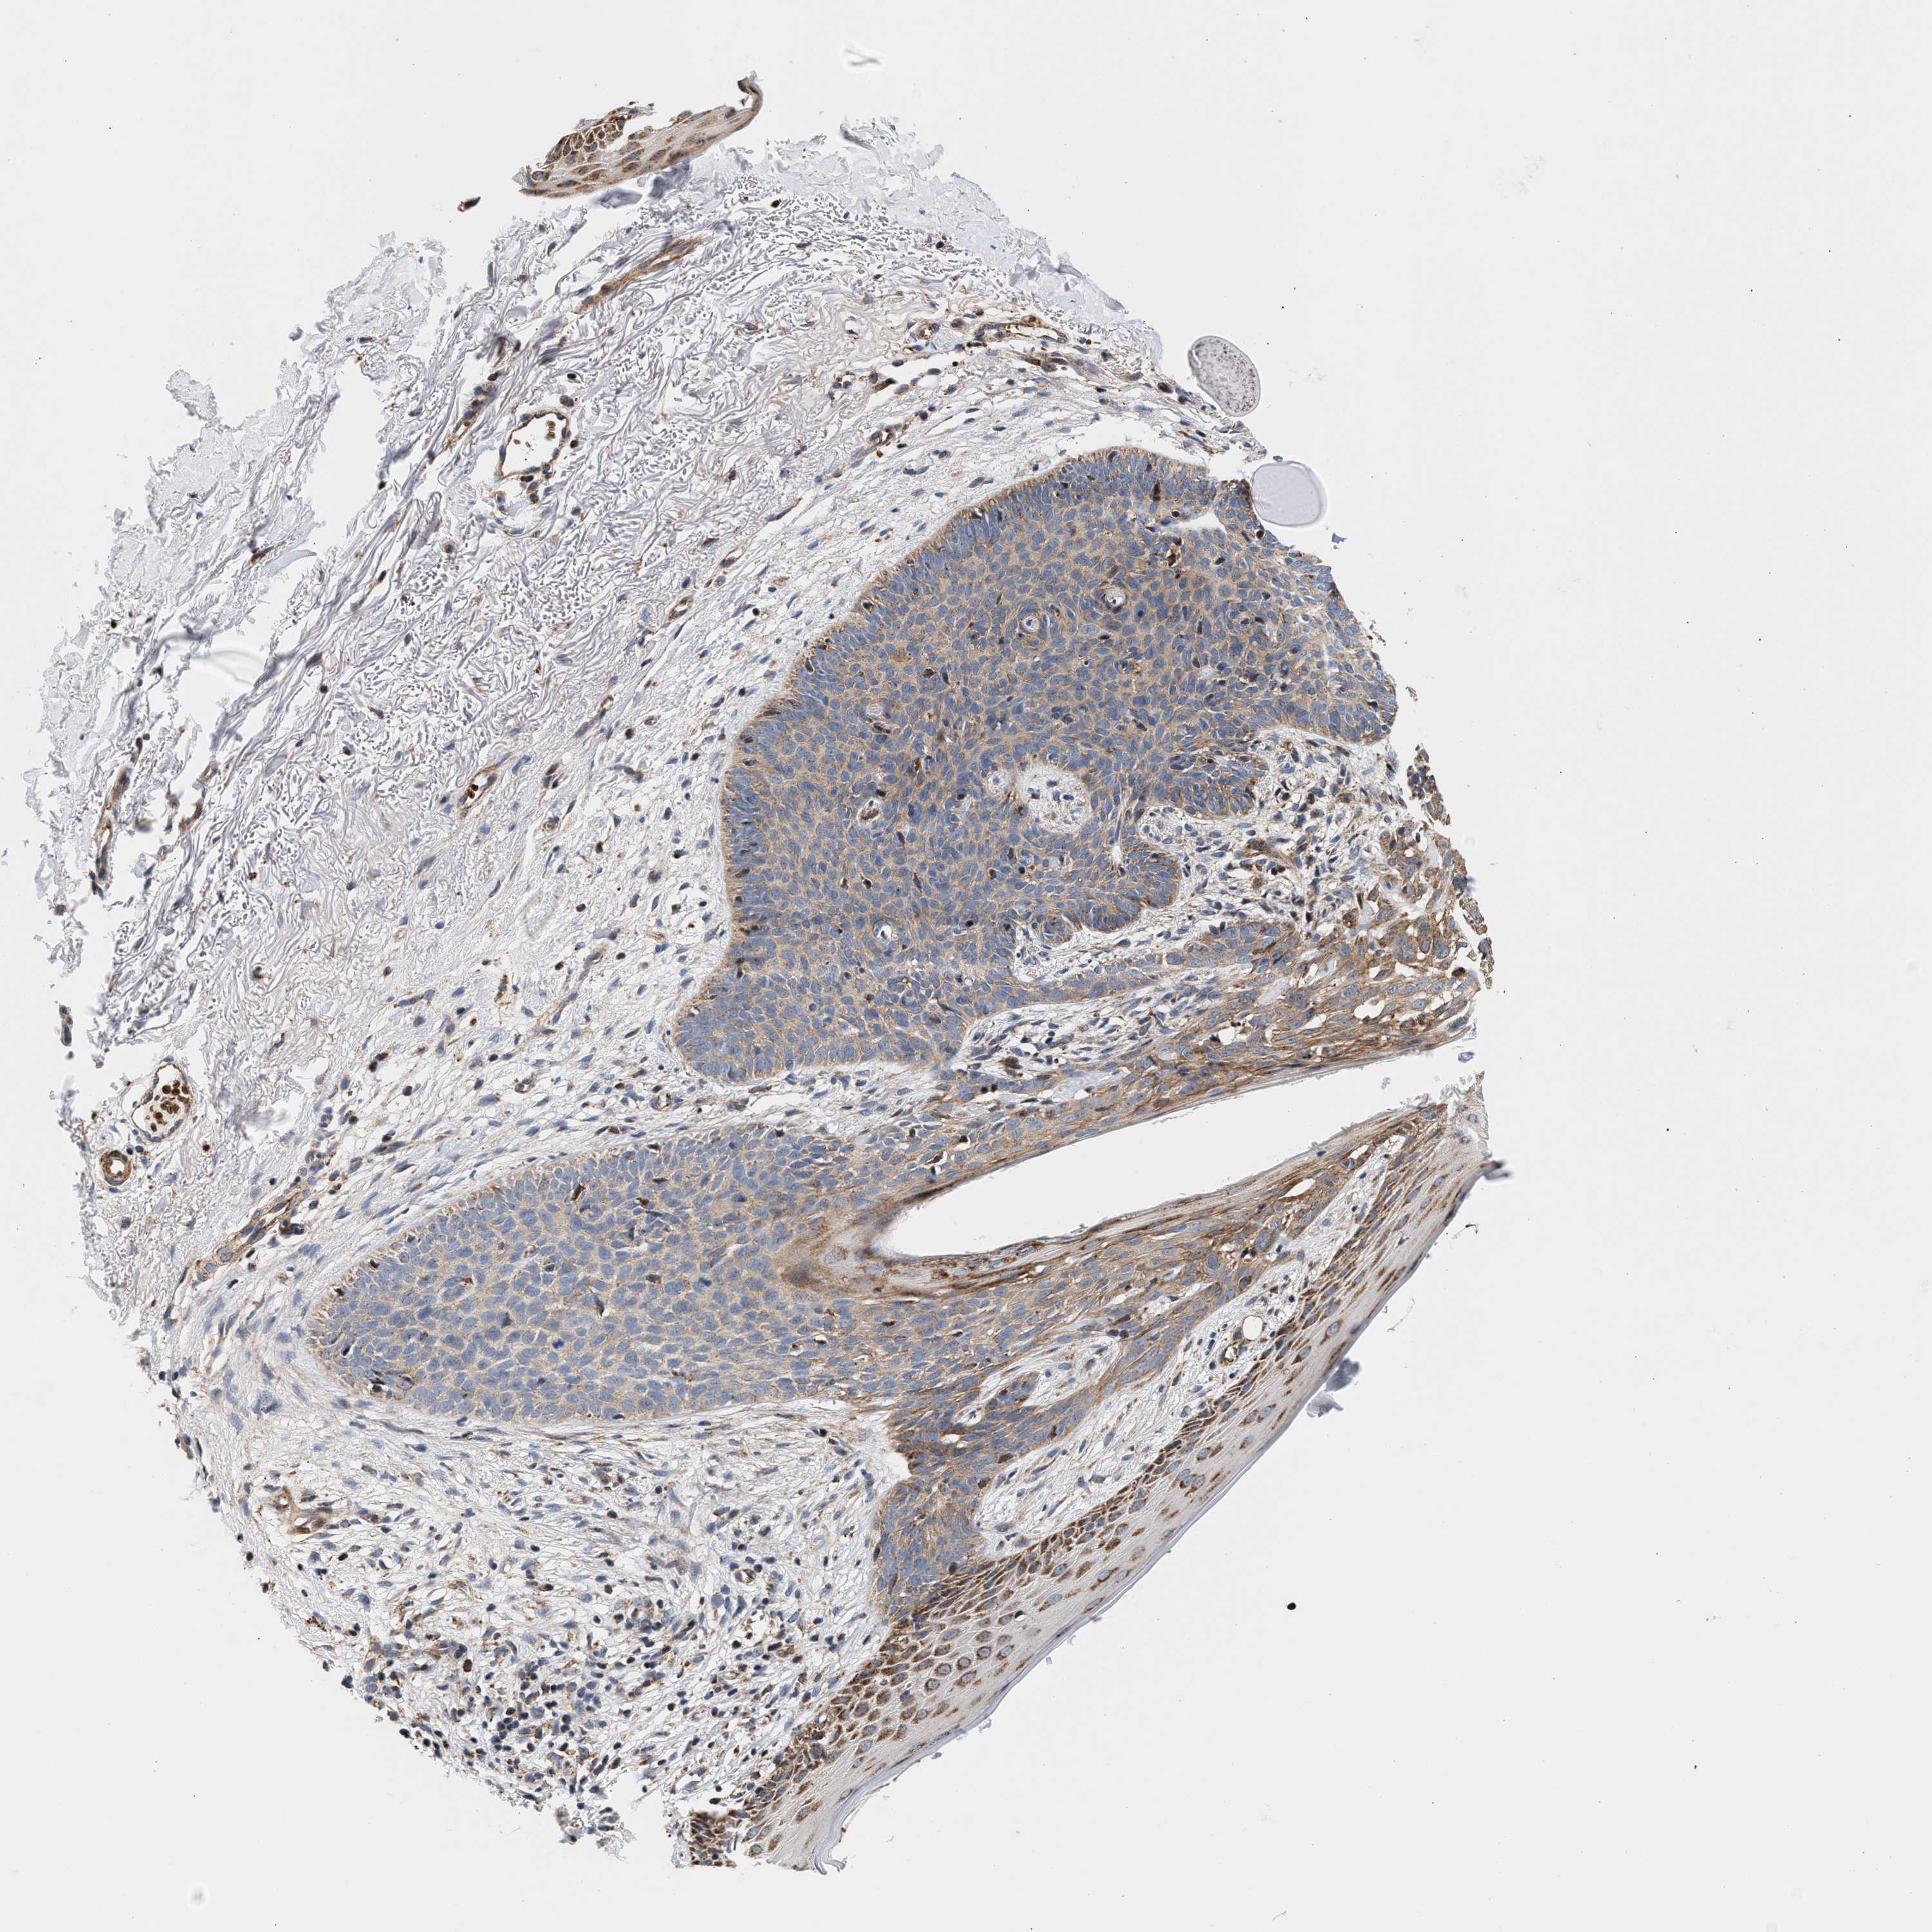

CANCER SKIN CANCER Show tissue menu

Basal cell and squamous cell cancer

SKIN CANCER - Protein expressioni

A mouse-over function shows sample information and annotation data. Click on an image to view it in a full screen mode. Samples can be filtered based on level of antibody staining by selecting one or several of the following categories: high, medium, low and not detected. The assay and annotation is described here.

Each image is clickable and will lead to virtual microscopy that enables deeper exploration of all samples and also displays staining intensity scores, fraction scores and subcellular localization as well as patient and tissue information for each sample.

Antibody CAB022085

Staining

High

Intensity

Strong

Quantity

>75%

Location

Nuclear

Squamous cell carcinoma, NOS